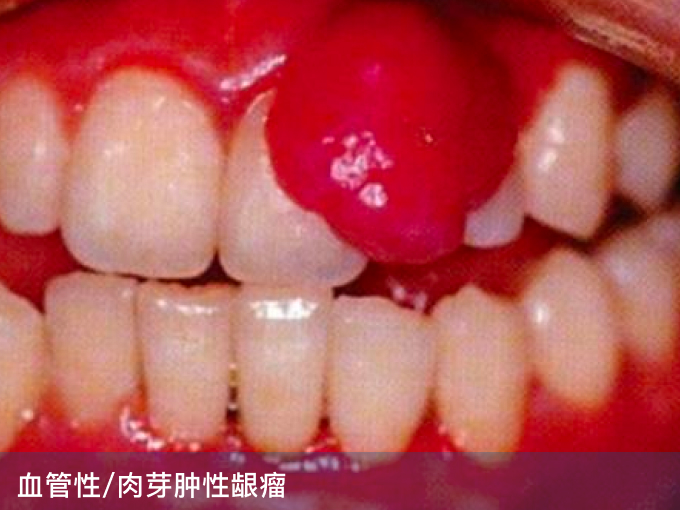

3、血管性/肉芽肿性龈瘤:病因可能与性激素改变有关,可表现为红色或紫红色包块,质软,触之易出血,多可自行消退,无法消退者可进行由医生手术切除。